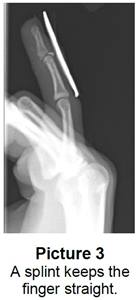

• It can sometimes break off a piece of bone. This is called a bony mallet (Picture 2). If the bone doesn’t break but the tendon tears, it’s called a soft tissue mallet.

Your child’s doctor or health care provider will ask what happened, examine the finger, and take an X-ray to see if the bone is broken.

• Splint or cast:  Your child may need to wear a splint or cast to keep their finger straight and in one position (Picture 3). For splints, your child:

• Needs to wear it for 24 hours a day for 6 to 8 weeks, even when bathing.

• May need to wear the splint longer than 2 months or at night.

• May take the splint off briefly after bathing, to dry the finger, but the fingertip must always stay straight